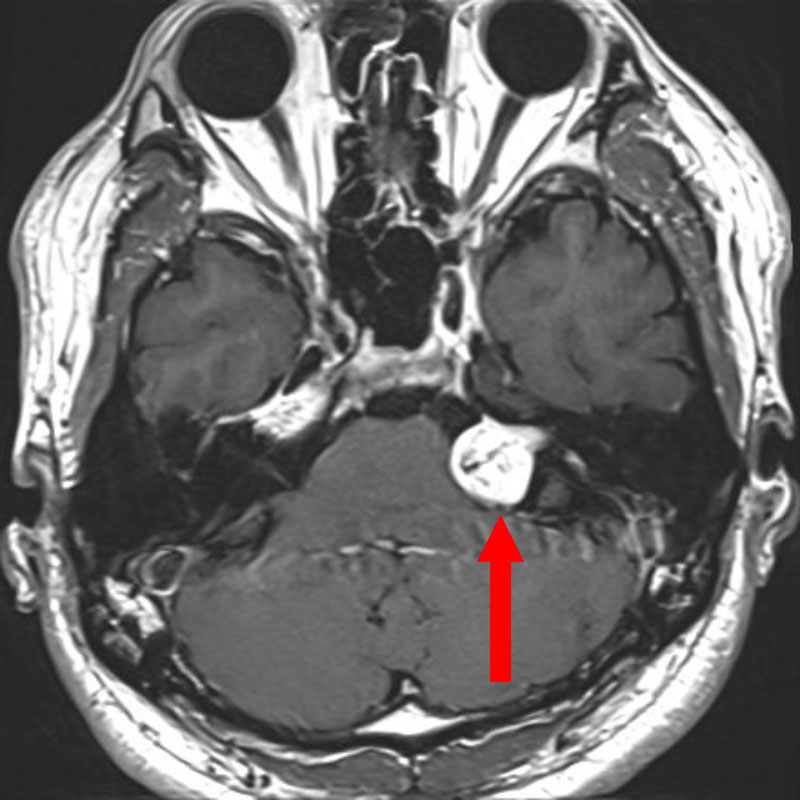

小脳腫瘍

頭蓋内腫瘍摘出術

No.’25_82 手術前1

No.’25_82 手術前2